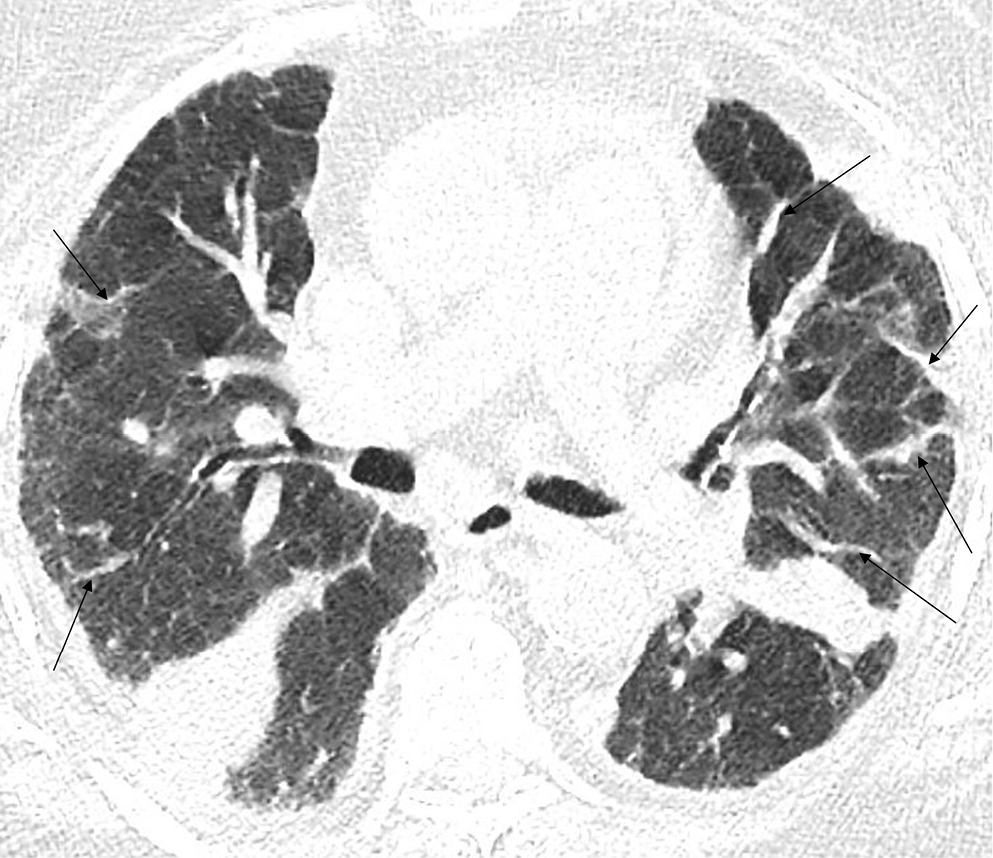

In the early stage of COVID-19, the primary CT findings observed are bilateral GGOs with a mostly peripheral and subpleural location. Ground-glass opacity is a term used to describe hazy areas with the preservation of vascular and bronchial margins which are a result of the partial filling of air spaces, intestinal thickening, or the coexistence of both (Figure 2).10 Another phenomenon is described as having ‘crazy-paving’ appearance. This is a combination of GGO and interlobular or intralobular septal thickening (Figure 3). This condition is mostly present in severe cases of COVID-19 pneumonia. Consolidations (multifocal, patchy or segmental) are another sign of COVID-19 progression (Figure 4).11 Several days after developing the first symptoms, chest CT can reveal linear consolidations and reversed halo signs in the patient’s lungs.12 Radiographic features typically include bronchovascular thickening (Figure 5).13

Based on similar research, 4 stages of CT imaging have been established. The 1st stage is named the early or initial stage and lasts up to 4 days. A CT scan performed during this period may not reveal any pathologies or may only indicate the presence of GGOs. It is crucial to remember that up to half of patients may have a normal CT scan 2 days after the symptoms occur. The next phase is the progressive stage (5–8 days) – several GGOs arise and the crazy-paving pattern becomes visible. Between 9 and 13 days, consolidations appear. This phase is called the peak stage. After 14 days, absorption begins and fibrous stripes may occur (Figure 6). After at least 1 month, and if no other complications arise, the patient’s lungs are able to return to a condition similar to that before COVID-19.16